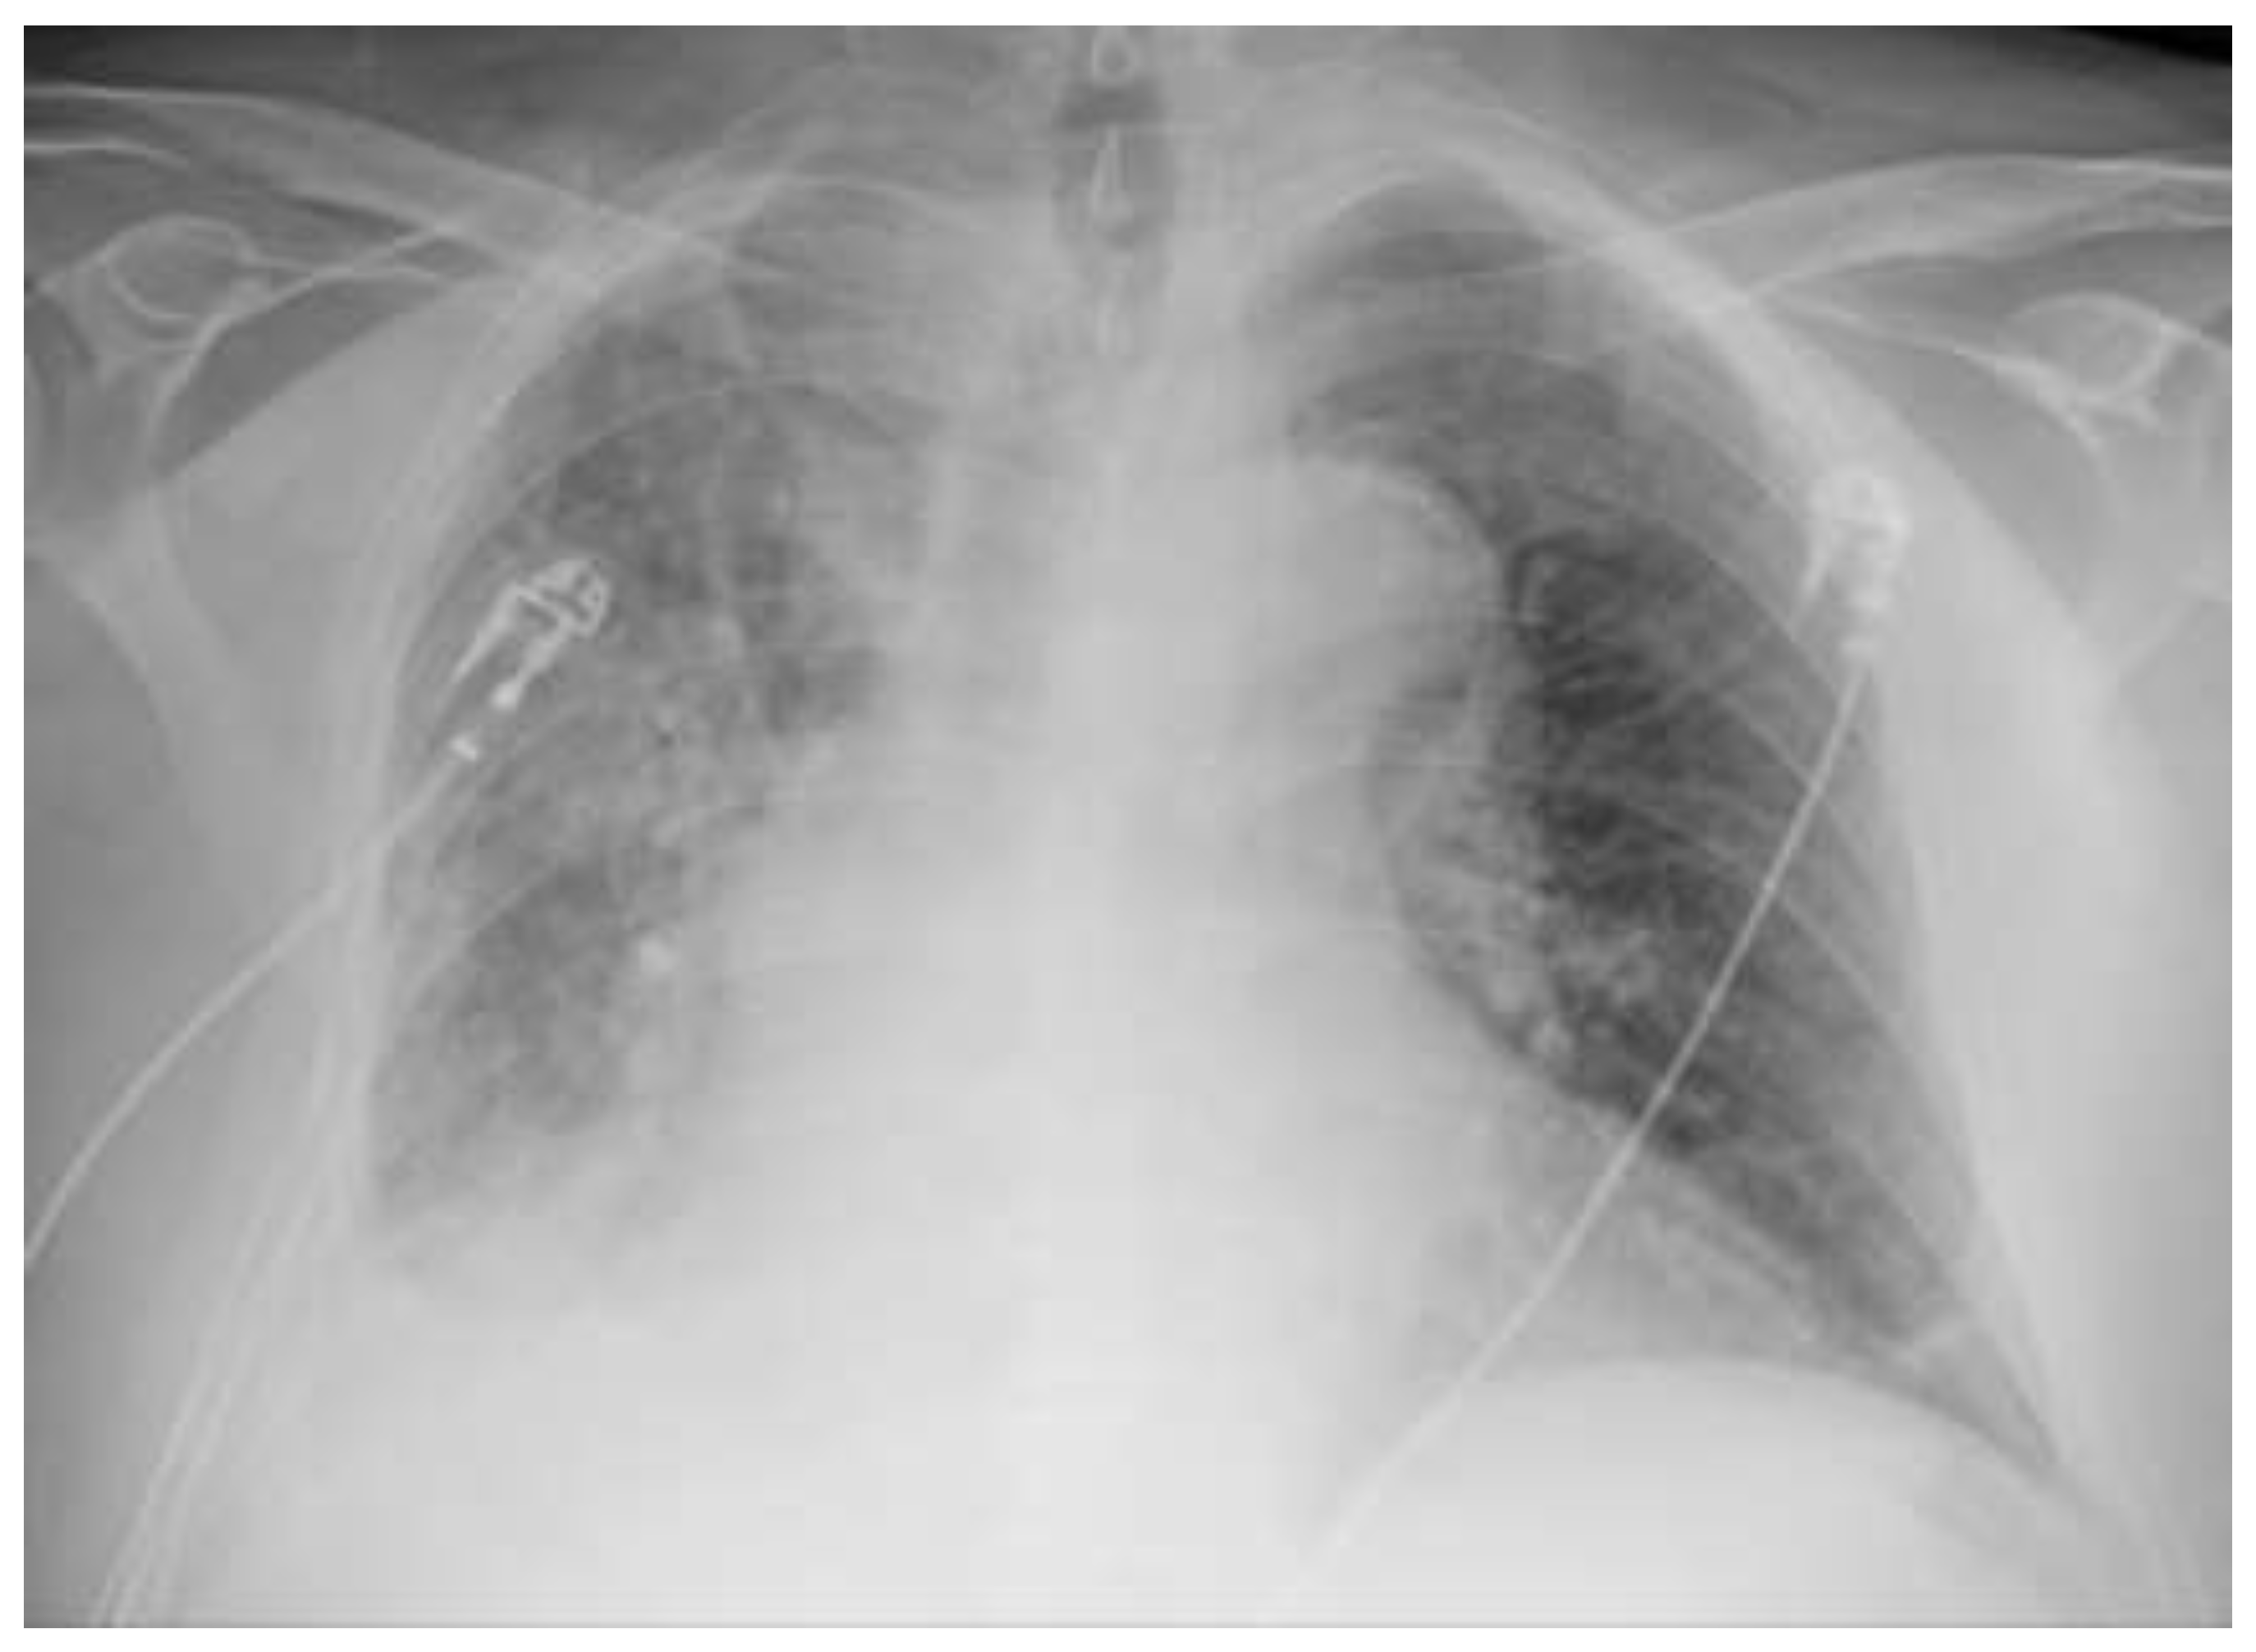

The patient’s respiratory failure remained critical during this phase and required the administration of high-dose oxygen supplement at up to 15 L/min via a Venturi mask to ensure adequate oxygenation. Microbiological testing on day 7 detected Micrococcus luteus, which was interpreted as contamination by the hospital laboratory. However, the radiological follow-up (chest radiograph on day 8) showed a significant improvement (Figure 3).

Figure 2. Follow-up chest X-ray (Day 8 post treatment initiation). Anteroposterior chest radiograph showing favorable dynamics, with partial resorption of the consolidation.